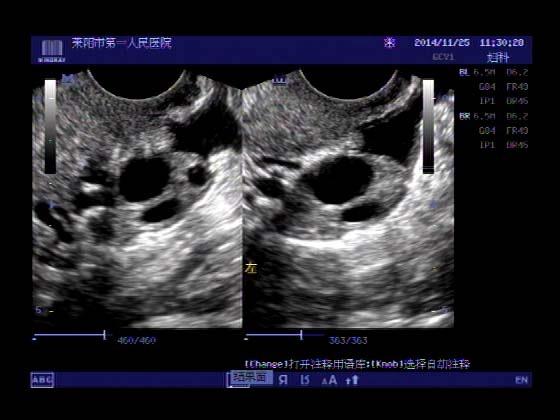

超声入门贴379---------粘膜下肌瘤(阴超的魅力)

女,43岁,月经量多3个多月,加重一个月

外院彩超检查提示:子宫后肌壁略高回声团------肌瘤?息肉?,盆腔少量积液

今天来我院检查:

巧妇难为无米之炊,经腹部超声确实很难定,阴超一目了然,乡镇医院诊断水平的提高更迫切的需要高档仪器的引进!